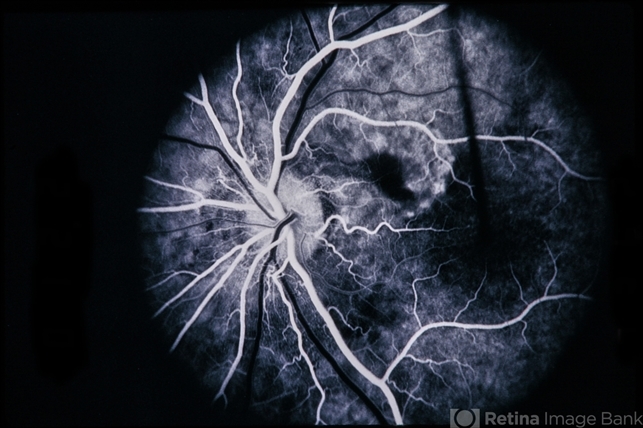

- Peripapillary CNVM Uveitis

- Condition/keywords

- peripapillary, choroidal neovascular membrane (CNVM), uveitis

- 4-year-old patient with peripapillary CNVM / uveitis.